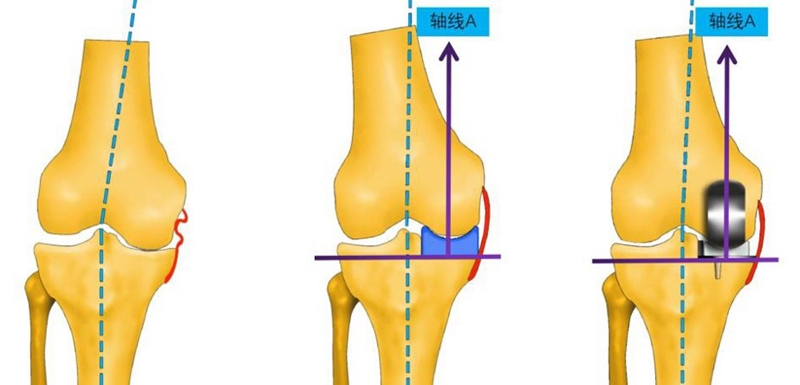

如何达到理想的垫片运动轨迹,一直是临床上难以解决的问题,中日友好医院团队在进行UKA手术时改良了运动学对位对线法技术,即给予胫骨截骨+下肢力线,股骨运动学对线定位的方法。

OUKA原理:充分填充,恢复自然。

伸直位外翻应力下内侧间隙打开

屈曲90°位外翻应力下内侧间隙打开

运动学对位对线定位技术的原理核心为:①胫骨精确截骨,保证力学;②spacer充分填充,恢复到自然状态。

操作要点(画好线,钻好孔)

①屈曲位,钻孔导向器底面紧坐在胫骨截骨面,贴住股骨远端;

②钻孔方向指向与轴线A平行;

③通过视窗核实钻孔贴于假体中心线上;

④钻孔位于股骨内髁远端关节面中心线。